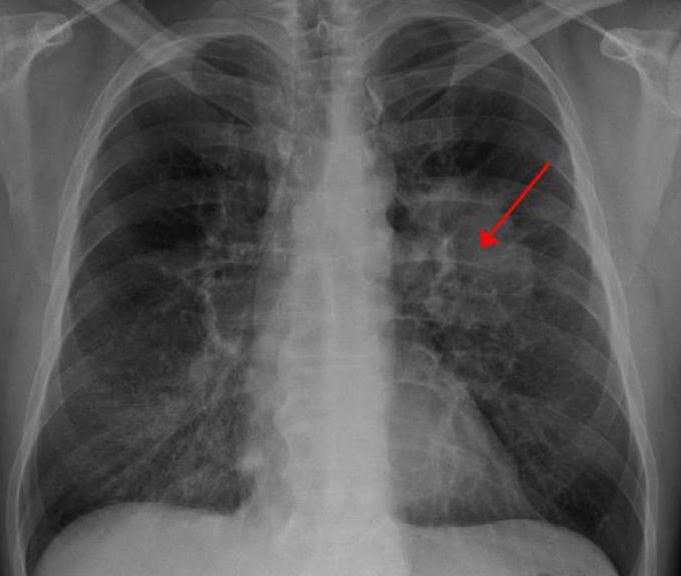

- Метод рентгенографии. Одним из самых первых способов диагностирования онкологического процесса в лёгких, наряду с флюорографией, признан рентгенографический снимок грудной клетки. Это обследование позволяет выявить очаги патологий, наличие уплотнений, процессы деформации лёгких, выраженность легочного рисунка;

Как узнать о наличии онкологии в лёгких, и каким образом можно ее диагностировать? Сегодня, почти шестьдесят процентов опухолей в лёгких можно обнаружить во время прохождения исследования флюорографией, которую рекомендуется делать один раз в два года, а еще лучше один раз в год. Также распространенными способами выявления рака лёгких являются: